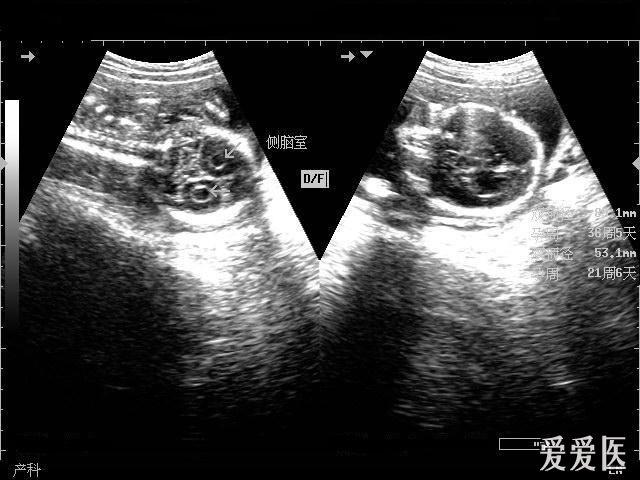

胎儿侧脑室超声图片,胎儿侧脑室测量图片

孕妇,孕33周,无明显不适,来我院检查,检查过程中发现胎儿侧脑室宽16

这例图片的胎儿颅内结构是正常的,箭头所指的是胎儿侧脑室,准确的

胎儿侧脑室测量图片